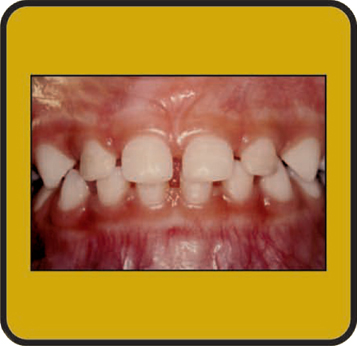

Find ugly duckling stock images in hd and millions of other royalty free stock photos illustrations and vectors in the shutterstock collection. Ugly duckling stage quick reference a stage of dental development usually between the ages of 7 and 12 years preceding the eruption of the permanent canines when the upper central and lateral incisors are tipped laterally due to the crowding created by the unerupted canines to produce a midline space median diastema. Ugly duckling download free clip art with a transparent background on men cliparts 2020.

55 ugly duckling image clipart. Ugly duckling stage is a transient form o. This video was uploaded from an android phone.